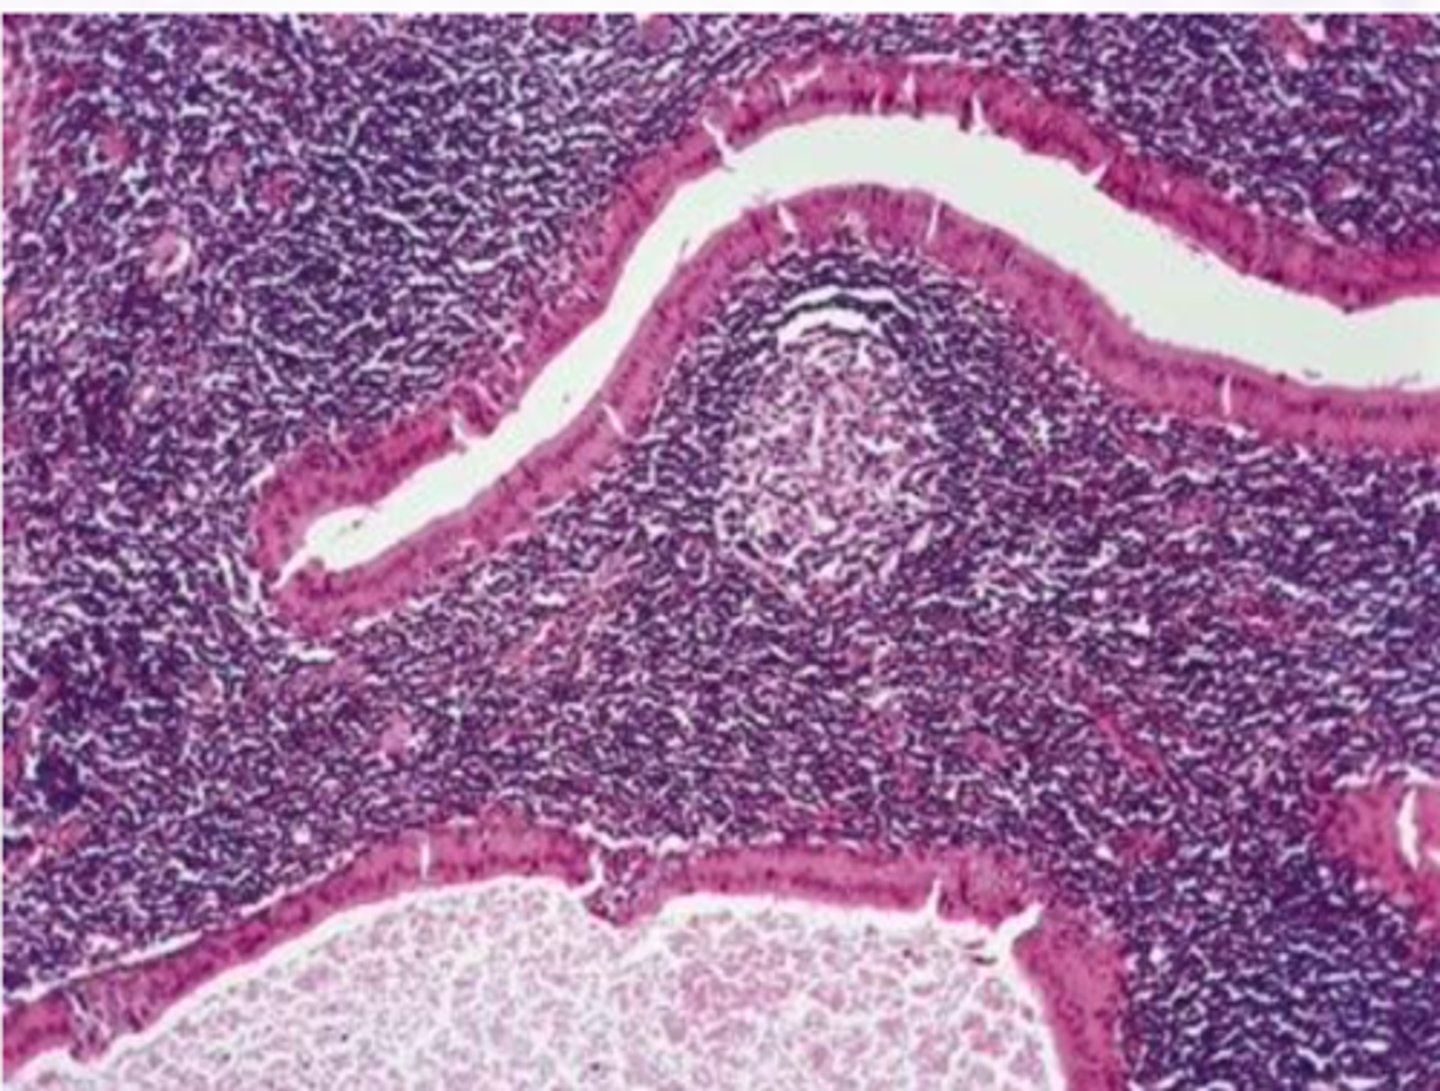

Warthin Tumor

Benign Salivary Gland Tumors:

-More common in males

-6th to 7th decades of life

-Association with smoking (8x)

-Slow growing painless mass of the parotid gland

-Proliferation of oncocytic cells and lymphoid cells

-Cyst lined by uniform rows of oncocytic cells

-The lining is papillary in appearance

-The cyst wall is composed of abundant lymphocytes

6-12%

Warthin tumor has what percent recurrence after surgical removal?